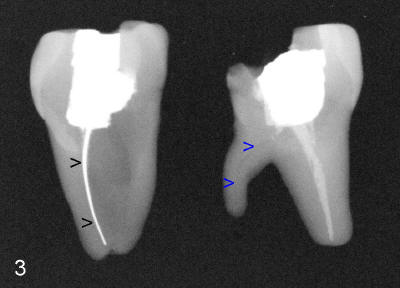

As discussed before, we plan to extract the affected tooth atraumatically by sectioning. When the distal portion of the tooth is taken out, there are two sockets distally (D, DL in Fig.1). There is an extra distal root (arrowhead in Fig.2). The mesial (M) and distal (D) portions of the tooth are laid out so that the buccal (B) is placed outside, lingual (L) inside of the photo. We are seeing the sectioned surfaces of the tooth. With the same arrangement, PA is taken (Fig.3). The silver cone (black arrowheads) is off the center of the mesial root, suggesting missing mesiolingual canal. The second missing canal, distolingual (blue arrowheads) is narrow and highly curvy. In fact the mesiolingual canal is also obliterated. It takes effort and time to go through it (Fig.4 black arrowhead). The distolingual canal is so obliterated that perforation is the end result (using rotary file) (blue arrowheads).